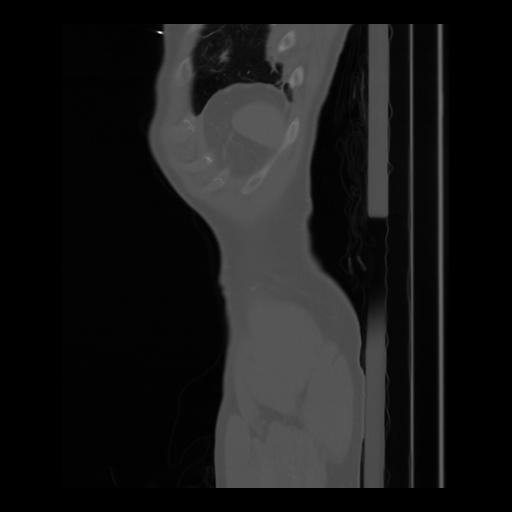

36 CUERPO,CE,Sagittal,3.000,CUERPO,Sagittal,